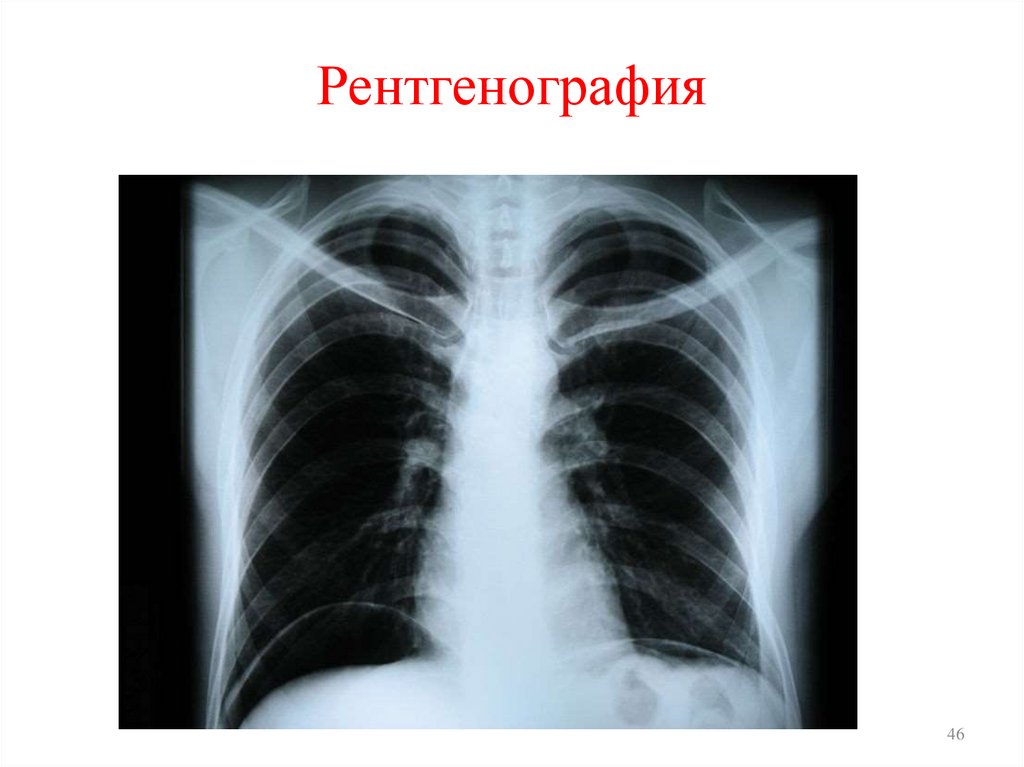

46. Рентгенография

• Рентгенография применяется с целью регистрации и